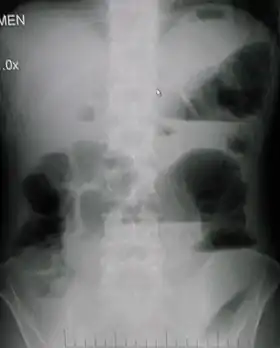

Рентгенологічне обстеження:

- Кишкові арки — тонка кишка роздута газами, в нижніх колінах арок видно горизонтальний рівень рідини, і його ширина менша ніж висота газового стовпа.

- Чаші Клойбера — горизонтальні рівні рідини з куполоподібними просвітами і мають вигляд перевернутої чаші.

- Симптом перистості (пружини) — при високій непрохідності, пов'язаний з набряком тонкої кишки.

Рентгенологічні ознаки: Обтураційна: товстокишкові чаші «Клойбера», в яких ширина рівня рідини менша за висоту газового пухиря над ним; пневматизація товстої кишки та її інтерпозиція, на фоні газу проглядається рельєф слизової оболонки товстої кишки — напівмісячні арки;

Странгуляційна: тонкокишкові арки з горизонтальними рівнями рідини — чаші «Клойбера», розтягнення керкрингових складок у вигляді пружини, відсутність пневматизації товстої кишки.

Рентгенологічні ознаки: Для динамічної непрохідності характерні: високе стояння та обмеження рухливості куполів діафрагми; велика кількість газу в атонічному шлунку, петлях тонкої і товстої кишок, рівномірне розташування та відсутність переміщення рідини в межах роздутої кишкової арки, відсутність розтягнення керкрингових складок у вигляді пружини.

Рентгенологічні ознаки кишкової непрохідності у дитини

Чаші Клойберга

Здуті петлі кишок